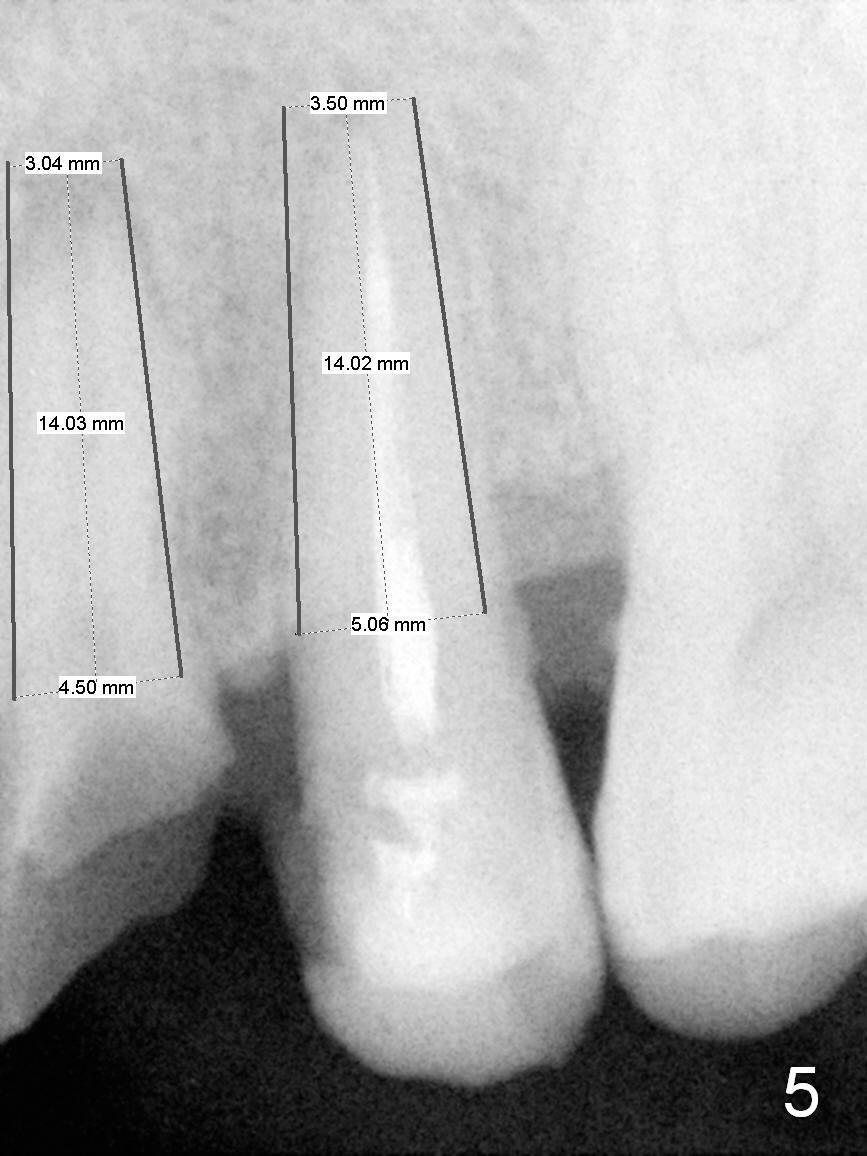

A 45-year-old man presented to our office 8 years ago (Fig.1,2) and got work done somewhere else. He returned yesterday with chief complaint "I might swallow my crowns". Exam shows residual roots at #12,13 (Fig.3,4). The patient has strong jaw bone, suggesting that the bone density is high. Either bone- (Fig.5) or tissue- (Fig.6) level implants will be placed. By time sequence, this case will be assigned to the control group of the antibiotic study. Preop PA does not catch the apices (Fig.3). Take a new one with sensor 1 prior to surgery or panoramus.